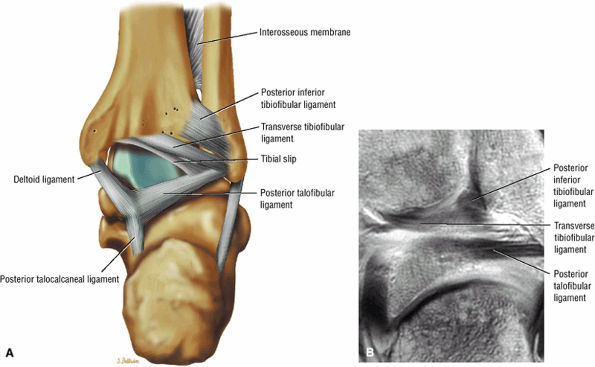

The syndesmotic ligaments consist of the anterior syndesmotic or anterior inferior tibiofibular ligament and the posterior syndesmotic or posterior inferior tibiofibular ligament, the interosseous membrane, and the transverse tibiofibular ligament.

-

The transverse tibiofibular ligament represents the posterior labrum of the ankle and projects inferior to the posterior tibial margin.

The tibial slip is the posterior intermalleolar ligament.

FIGURE 5.66 ● (A) A posterior view of the ankle joint shows the articular surface of the talus after removal of the capsule. (B) The posterior ankle ligaments in the right ankle. The thick structure to the left is the posterior inferior tibiofibular ligament. The structure to the right is the transverse tibiofibular ligament. In this picture, the tibia is on top and the talus is below.